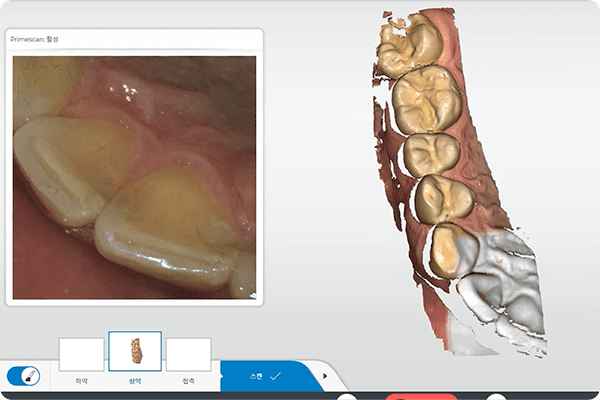

3D 입체스캐너

3차원 디지털 치아스캔 장비를 통해 빠른 시간 내에 편안하게

구강 내를 촬영하며, 구강 내 환경을 정확하게 재현해 냅니다.

핵심기술 02

3D CT&디지털 치아 스캐너 정밀 진단3D CT와 치아 스캐너의 데이터를 결합하여, 임플란트를 실제로 심었을 때 가장 이상적인 위치에 식립될 수 있도록 지향합니다.